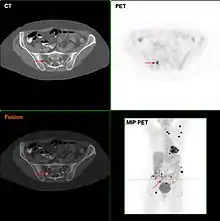

غالبا ما يستخدم نازعة الاكتات (إنزيم نازع لهيدروجين اللاكتات) (LHD) لاختبار الكشف عن النقائل، على الرغم من ان المرضى الذين يعانون من الانبثاث (حتى نهاية المرحلة) لديهم نازعات الاكتات الطبيعي غالبا ما يشير بشكل غير عادي إلى ارتفاع انتشار المرض المنتشر في الكبد. ومن الشائع للمرضى تشخيص الميلانوما ان يكون الصدر بالاشعة السينية واختبار LHD وفي بعض الحالات CT،MRI،PETو / أو مسحPET / CT. على الرغم من الجدل، يتم تنفيذ فحص الغدد الليمفاوية في المرضى لتقييم انتشارها اليها ويدعمتشخيصالميلانومابنسبةحضورS-100البروتينعلامة. HMB-45 هو من الاجسام المضادة احادي النسيلة ان يتفاعل ضد المستضد الموجود في الاورام الميلانينية مثل الميلانوما، وتقف على الانسان الميلانوما السوداء والتي يتم استخدامها في علم الامراض التشريحي كعلامة لمثل هذه الاورام. تم انشاء الاجسام المضادة لاستخراج الميلانوما. يتفاعل بشكل ايجابي ضد اورام ميلانينية ولكن ليس اورام اخرى، وبالتالي خصوصية وحساسية. وتتفاعل الاجسام المضادة ايضا ضد خلايا الشامات ولكن ليس داخل شامات الأدمة وضد اجنة الخلايا الصباغية ولكن ليس الخلايا الصباغية البالغة الطبيعية.

الميلانوما عالية المخاطر قد تتطلب العلاج المساعد على الرغم من التوجهات لهذا قد تختلف باختلاف البلدان. في الولايات المتحدة فان معظم المرضى في صحة جيدة، تبدأ جرعة عالية من العلاج "الانترفيرون" تصل إلى عام والتي لها اثار جانبية خطيرة ولكن قد تتحسن احوال المريض قليلا.[40] لكن الجمعية البيريطانية للمبادئ التوجيهية لامراض الجلدية في حالة الميلانوما ان الانترفيرون لا ينصح كعلاج مساعد للميلانوما.[41] وفي عام 2011 استخلص من التحليل ان الانترفيرون يمكن ان يطيل الوقت قبل ان تعود الميلانوما مرة اخرى ولكن تزيد نسبة البقاء على قيد الحياة بنسبة 3% لمدة 5 سنوات والاثار غير السارة ايضا تقلل نوعية الحياة إلى حد كبير.[42] في أوروبا عادة لا يتم استخدام الانتروفيرون خارج نطاق التجارب السريرية.[43][44] ويمكن الكشف عن الأورام الميلانينية المتنقله بواسطة الأشعة السينية و المقطعية، الرنين المغناطيسي و التصويرPETوPET / CTS و الموجات فوق الصوتية واختبار LDH و الكشف الضوئي.[45]